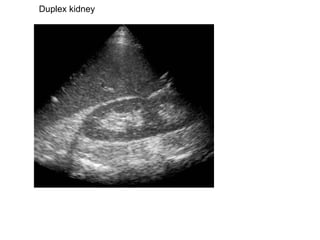

Duplex kidney